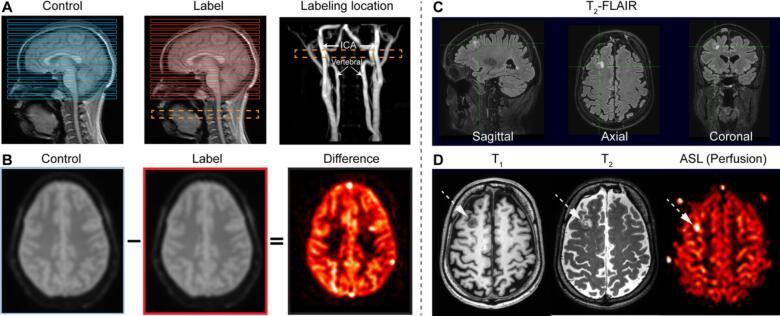

Tumor hypoxia indicates a worse prognosis in brain malignancies; however, current gold-standard methods for assessing tumor hypoxia are invasive and often inaccessible. Magnetic Resonance Imaging (MRI) is widely available, but its validity for identifying tumor hypoxia or hypoxia-related neoangiogenesis is not well characterized. A systematic literature search was performed across PubMed and Embase Databases. The search query identified MRI studies that validated hypoxia-surrogate imaging sequences against gold-standard hypoxia or neoangiogenesis detection methods in patients with brain malignancies. Literature screen identified 23 manuscripts published between 2007 and 2022. Among conventional MRI sequences, peritumoral edema and signal change after contrast administration were associated with gold-standard oxygen-assessment methods. T2*- and T2'-derived measures were associated with gold-standard methods, while reports on quantitative measures of oxygen extraction fraction were conflicting. Fiber density, tissue cellularity, blood volume, vascular transit time, and permeability measurements were associated with gold-standard methods, whereas blood flow measurements yielded conflicting results. MRI measures are promising surrogates for tumor hypoxia or hypoxia-related neoangiogenesis. Additional studies are needed to reconcile disparate findings. Future sensitivity analyses are needed to establish the MRI methods most accurate at identifying tumor hypoxia.

肿瘤缺氧表明脑恶性肿瘤的预后较差;然而,目前评估肿瘤缺氧的金标准方法具有侵入性,且常常难以实施。磁共振成像(MRI)应用广泛,但其在识别肿瘤缺氧或缺氧相关新生血管生成方面的有效性尚未得到充分表征。我们在PubMed和Embase数据库中进行了系统的文献检索。检索查询确定了一些MRI研究,这些研究在脑恶性肿瘤患者中针对金标准缺氧或新生血管生成检测方法验证了缺氧替代成像序列。文献筛选确定了2007年至2022年间发表的23篇手稿。在传统MRI序列中,瘤周水肿和注射造影剂后的信号变化与金标准氧评估方法相关。基于T2*和T2′的测量与金标准方法相关,而关于氧提取分数定量测量的报告则相互矛盾。纤维密度、组织细胞密度、血容量、血管通过时间和通透性测量与金标准方法相关,而血流测量结果相互矛盾。MRI测量有望成为肿瘤缺氧或缺氧相关新生血管生成的替代指标。需要进行更多研究来协调不同的研究结果。未来需要进行敏感性分析,以确定在识别肿瘤缺氧方面最准确的MRI方法。